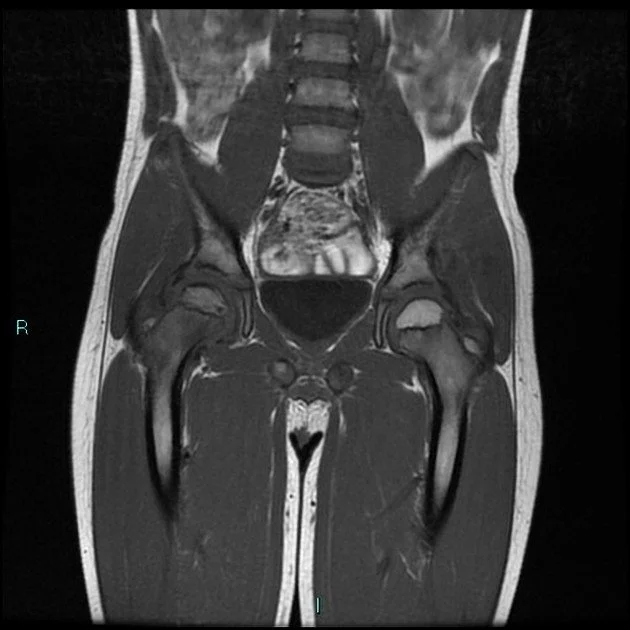

Standing MRI in children with Legg-Calve Perthes Disease (LCPD)

We have initiated a novel study to investigate the utility of standing MRI scans of hips affected by LCPD in children. The Centre for Hip Health and Mobility has the only research-dedicated upright MRI scanner of its kind in the world. The preliminary findings demonstrate the feasibility of upright MRI scanning and may reveal previously undetected hip deformities.